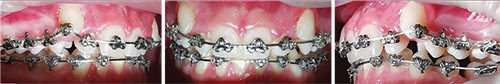

On Feb. 3, the Fastbraces were removed and lingual fixed retainers were cemented from canine to canine in both arches. The case finished with the canines in a Class I relation and an ideal overbite/overjet relationship. The patient was very happy with the result (Fig. 9).

Fig. 9: Feb. 3; final results